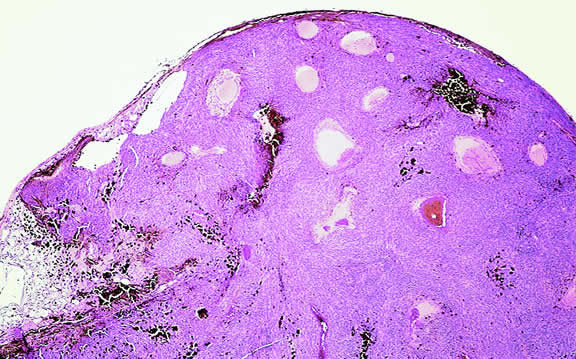

Gross Pathology

Choroidal melanomas initially arise in the stroma of the choroid. In early cases, the profile of the sectioned tumor is oval or almond-shaped, and its tissue usually appears relatively cohesive after fixation (Fig. 24). Although some tumors diffusely infiltrate the uvea, most uveal melanomas are relatively well-circumscribed tumors with distinct margins. In many cases the growing melanoma perforates Bruch's membrane and enters the subretinal space where its apex typically assumes a spherical shape that often is likened to a mushroom or collar button (see Figs. 19 to 22.). Dilated vessels often are found in the mushrooming head of the tumor because the ends of Bruch's membrane exert a compressive cinch-like effect on the waist of the tumor (see Fig. 22). Rupture of Bruch's membrane was present in 87.7% of 1527 large- or medium-sized melanomas examined in the COMS.84 Retinal invasion was present in nearly half (49.1%), and tumor cells were found in the vitreous body in one fourth.

Fig. 24. Cut surface of heavily pigmented choroidal melanoma is almond-shaped. Bruch's membrane is intact.

Uveal melanomas vary markedly in their pigment content. Some tumors are totally amelanotic; others are maximally pigmented. In some instances, distinct clones of tumor cells that vary in pigment content are evident on gross examination or even clinically (Fig. 25). A friable or granular appearance of the cut surface of a melanoma noted during gross examination may be indicative of necrosis or a tumor rich in poorly cohesive epithelioid cells. Melanomas that contain cystic cavities occasionally are encountered.85

Fig. 25. Large dome-shaped ciliochoroidal melanoma is partially amelanotic. Bruch's membrane is intact.

About 3% of melanomas have a diffuse growth pattern. These relatively flat tumors grow laterally without thickening the choroid.86,87 Most are about 2 mm in thickness. Diffuse melanomas often are of mixed cell type and, compared with localized lesions, are more apt to infiltrate the sclera and invade the optic nerve or orbit (Fig. 26). Delayed diagnosis or misdiagnosis is common.

Fig. 26. Diffuse choroidal melanoma thickens choroid. Massive invasion of optic nerve is seen at left. (Hematoxylin-eosin, × 50.)

Choroidal melanomas are classified as small, medium, or large based on the largest tumor diameter (LTD). Small choroidal melanomas are 10 mm in diameter or less and appear as focal discoid or oval areas of choroidal thickening. Medium-sized melanomas measure 11 to 15 mm, and large tumors are more than 15mm in largest basal tumor diameter. Larger tumors are more likely to have ruptured through Bruch's membrane.